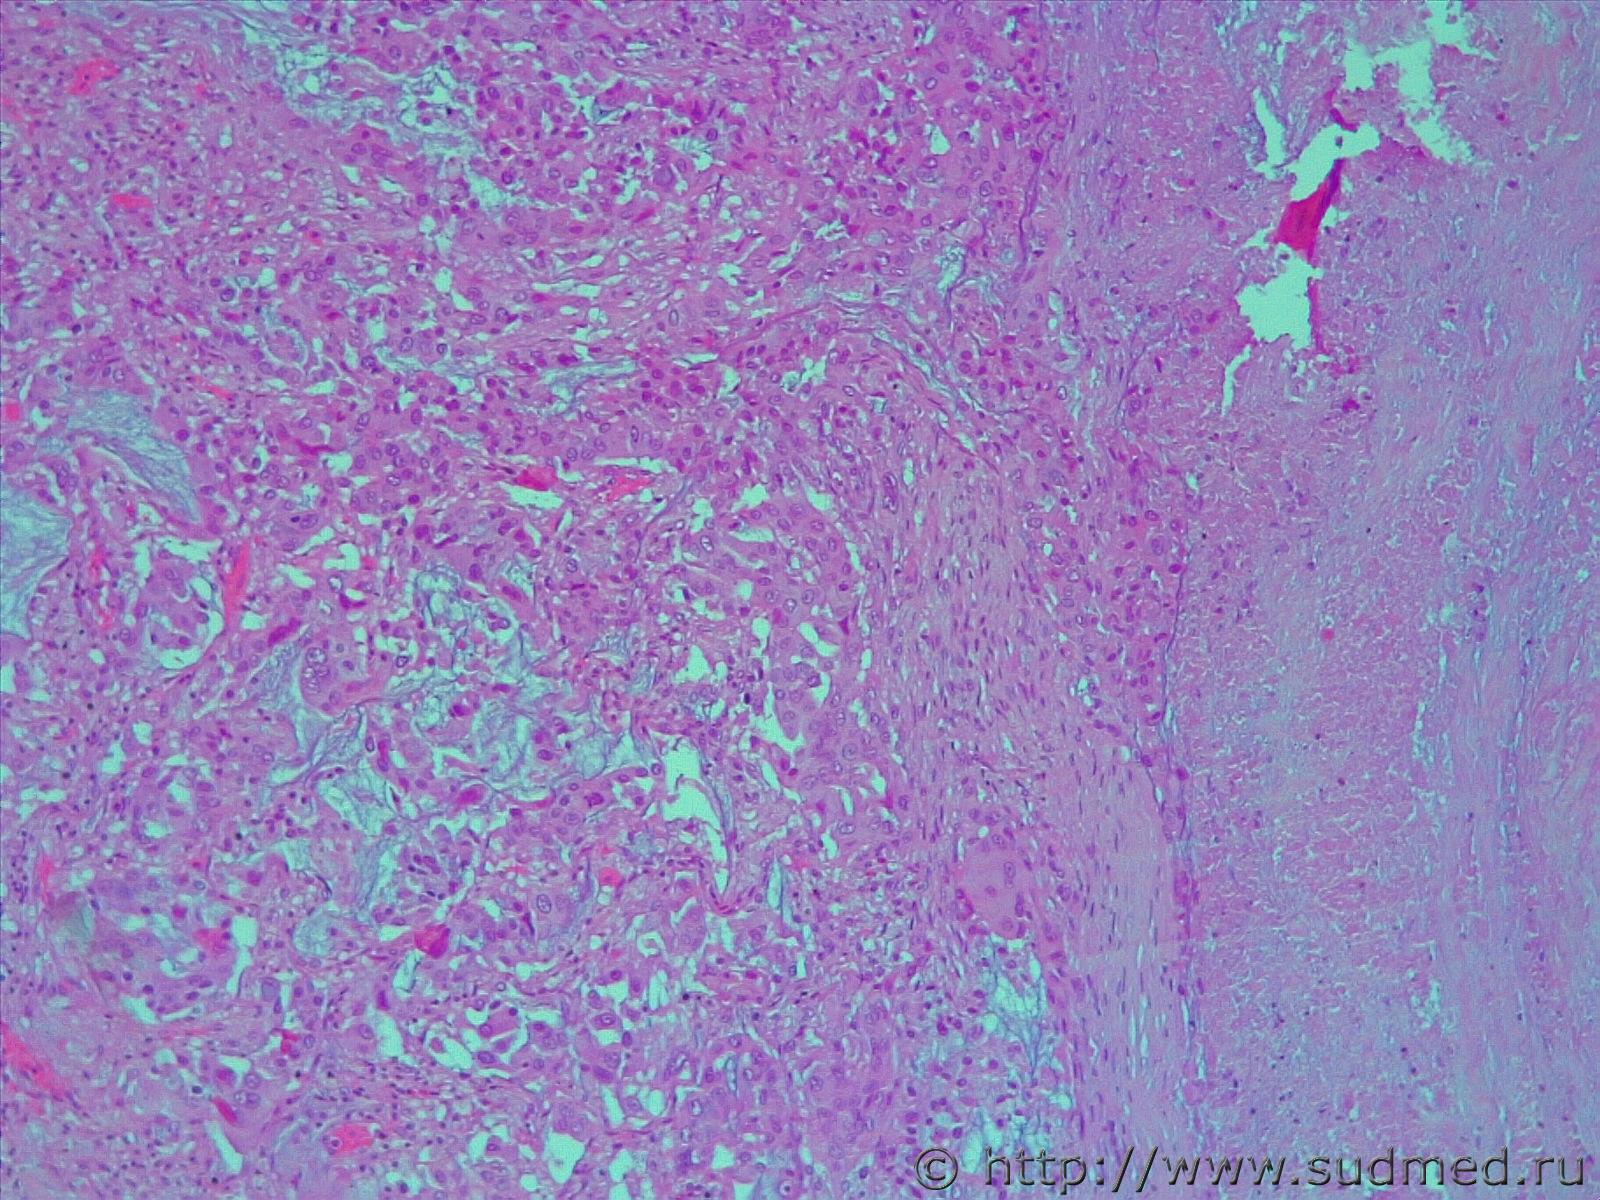

подскажите пожалуйста с опухолью.. совсем туго идет

Могу лишь предположить н/д аденокарциному со слизеобразованием

Фото не увеличиваются, но можно предположить, что это аденокарцинома.